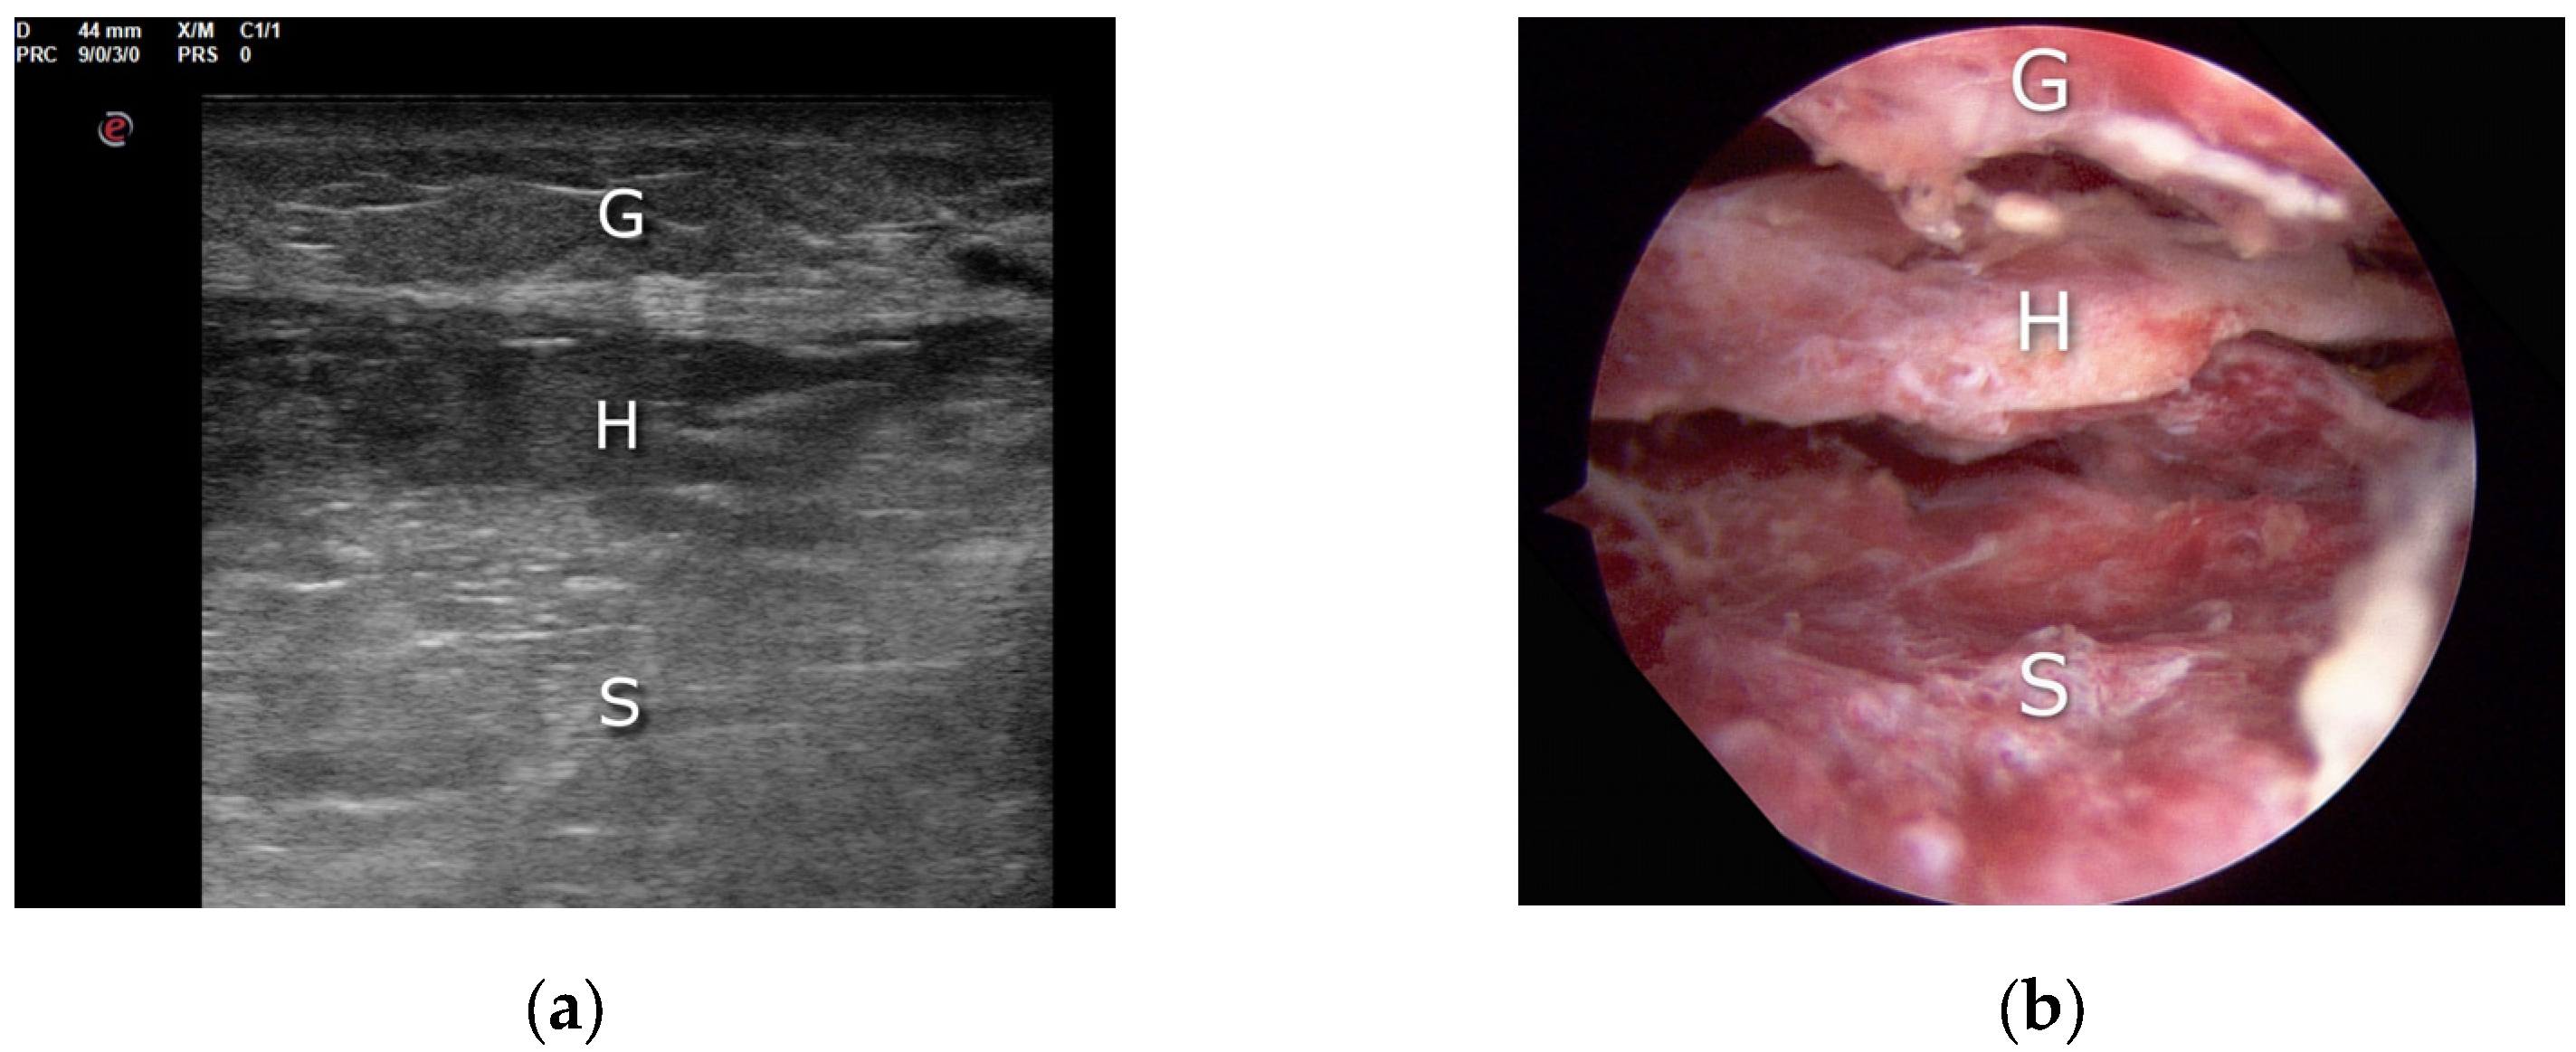

- Villanueva, M.; Iborra, Á.; Rodríguez, G.; Sanz-Ruiz, P. Ultrasound-Guided Gastrocnemius Recession: A New Ultra–Minimally Invasive Surgical Technique. BMC Musculoskelet. Disord. 2016, 17, 409. [Google Scholar] [CrossRef] [PubMed]

- Schroeder, S.M. Uniportal Endoscopic Gastrocnemius Recession for Treatment of Gastrocnemius Equinus with a Dedicated EGR System with Retractable Blade. J. Foot Ankle Surg. 2012, 51, 714–719. [Google Scholar] [CrossRef]